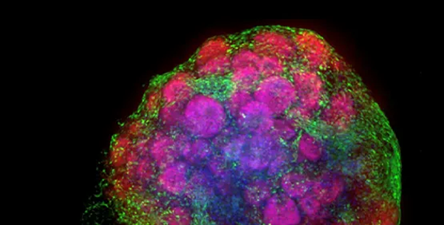

3D Brain (cerebral, neural) organoids

Image Credit: Molecular Devices UK Ltd

Brain organoids are 3D tissue models depicting one or more brain areas. They can overcome the limitations of traditional post-mortem and animal brain models to generate clinically useful results.

Cerebral organoids have enormous promise for studying brain development and neuronal disorders. They can also be used to study genetic abnormalities and the impact of chemicals. Nonetheless, capturing the distinctness of the human brain necessitates functional assays and high-content imaging techniques.